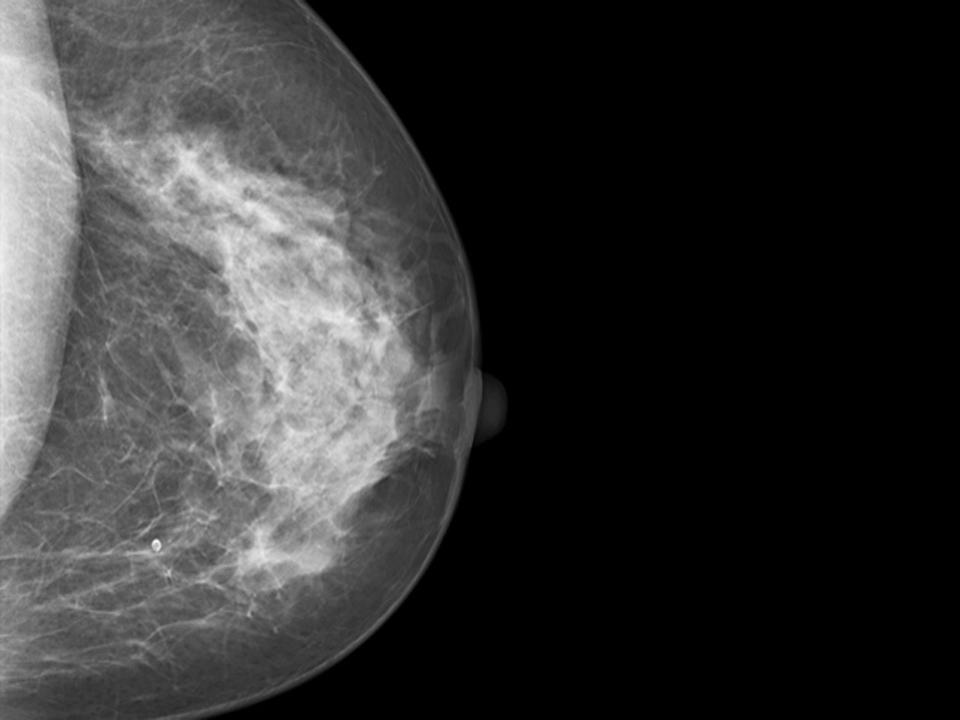

Clear analysis of dense breast tissue